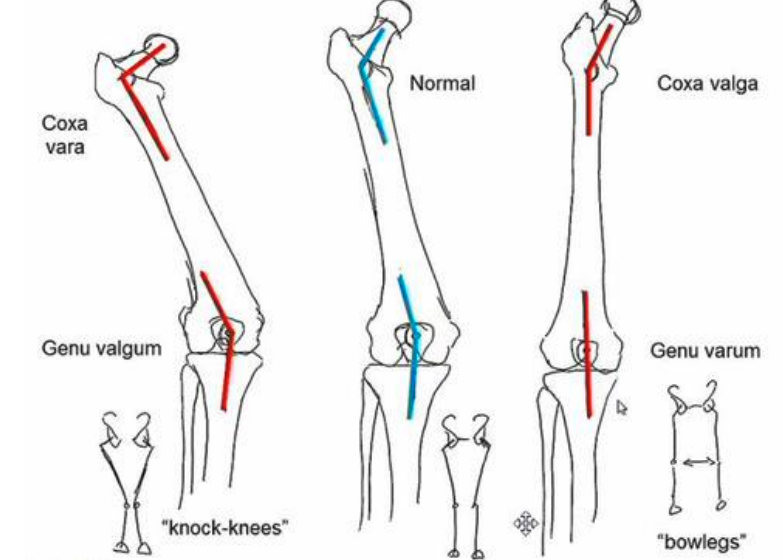

varus

an angulation of a distal segment towards the midline of the body relative to the normal ranges

valgus

an angulation of a distal segment away from the midline of the body relative to the normal ranges

angle of inclination

-angle between the femoral neck and femoral shaft in the frontal plane

-adult normal ~125 degrees

-decreased angle = coxa vara <125

-increased angle = coxa valga >125 degrees

Clinical implications of coxa valga

-angle of inclination is > normal

-decreases abduction moment arm leading functionally weakened hip and increased joint reaction force

-decreased stability due to lessened coverage of the femoral articular surface with the acetabulum

-prediposes to hip dislocation

LE chain effects of coxa valga

-less stability

-shallow acetabulum

-abducted hip

-genu varum at the knee

-supination of the foot

-longer limb

clinical implications of coxa vara

-increased hip joint stability

-increases moment arm of abductors (functionally stronger hip) reduces joint reaction force

-increase bending moment across femoral neck predisposition for (slipped capital femoral epiphysis or femoral neck fracture)

LE Chain effect of Coxa Vara

increased shear force across the femoral neck, adducted hip, valgus knee, pronation at foot, shorter limb